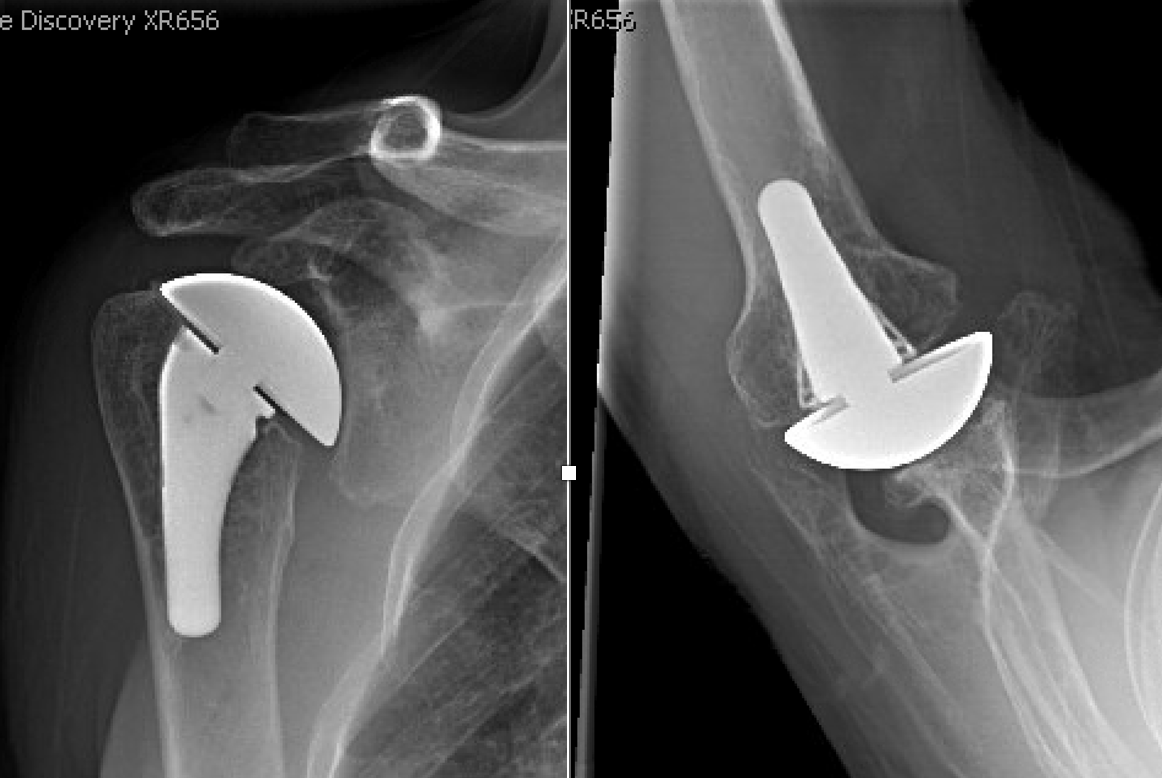

Four recently published articles provide important new information about the ream and run procedure for active patients with shoulder arthritis Those readers interested in learning more can access a discussion of these new articles here: shoulderarthritis.blogspot.com/2026/03/cocr-r…